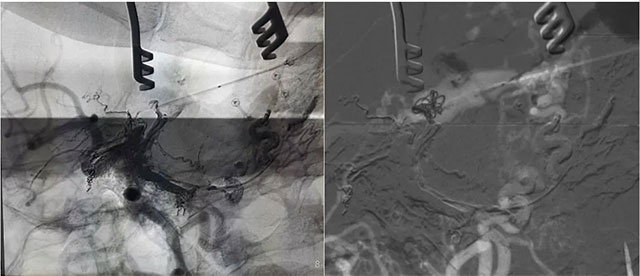

▲ 微导管造影确认后,注入 Onyx 18胶 5ml

经左侧股动脉以单弯造影管超选至左侧颈总动脉造影明确静脉穿刺点入路,予以穿刺针穿刺成功后造影明确在位,随后 Echelon 10微导管到位横窦,填入一枚弹簧圈做塞子,造影明确位置后,缓慢注入 Onxy18胶 5毫升,铸胶弥散良好,通过静脉逆向弥散至部分供血动脉内。复查造影,见瘘口完全被栓塞,引流静脉消失,手术成功。

术后患者临床症状消除,精神矍铄,现正在康复中。

▲ 术后影像